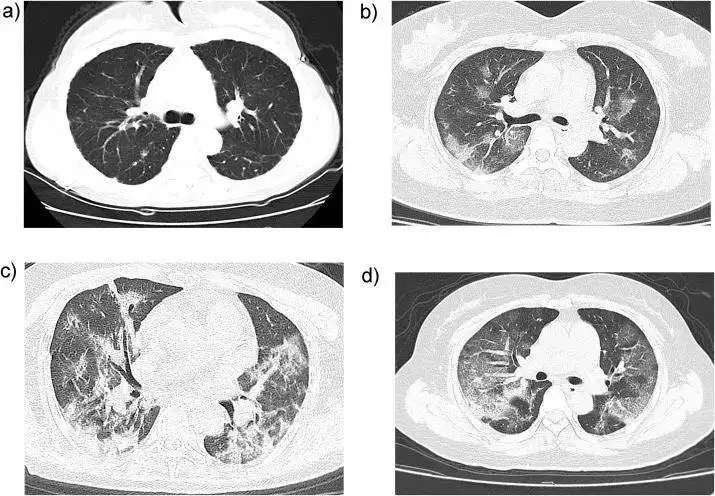

新冠肺炎患者的CT表現(xiàn),早期多呈現(xiàn)多發(fā)的小斑片影及間質(zhì)的病變

以肺外帶明顯,會逐漸發(fā)展為雙肺多發(fā)的磨玻璃影、浸潤影。

嚴(yán)重的患者會出現(xiàn)肺的實(shí)變影像,以及胸腔積液。